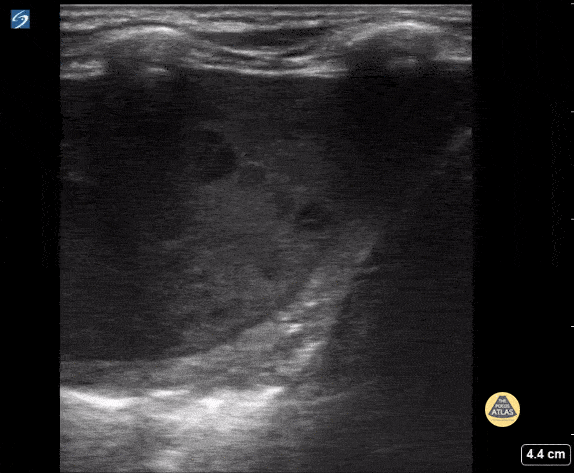

15 year old with complex PMH who presented with respiratory distress. CXR shows a large effusion. Bedside ultrasound showed an empyema.